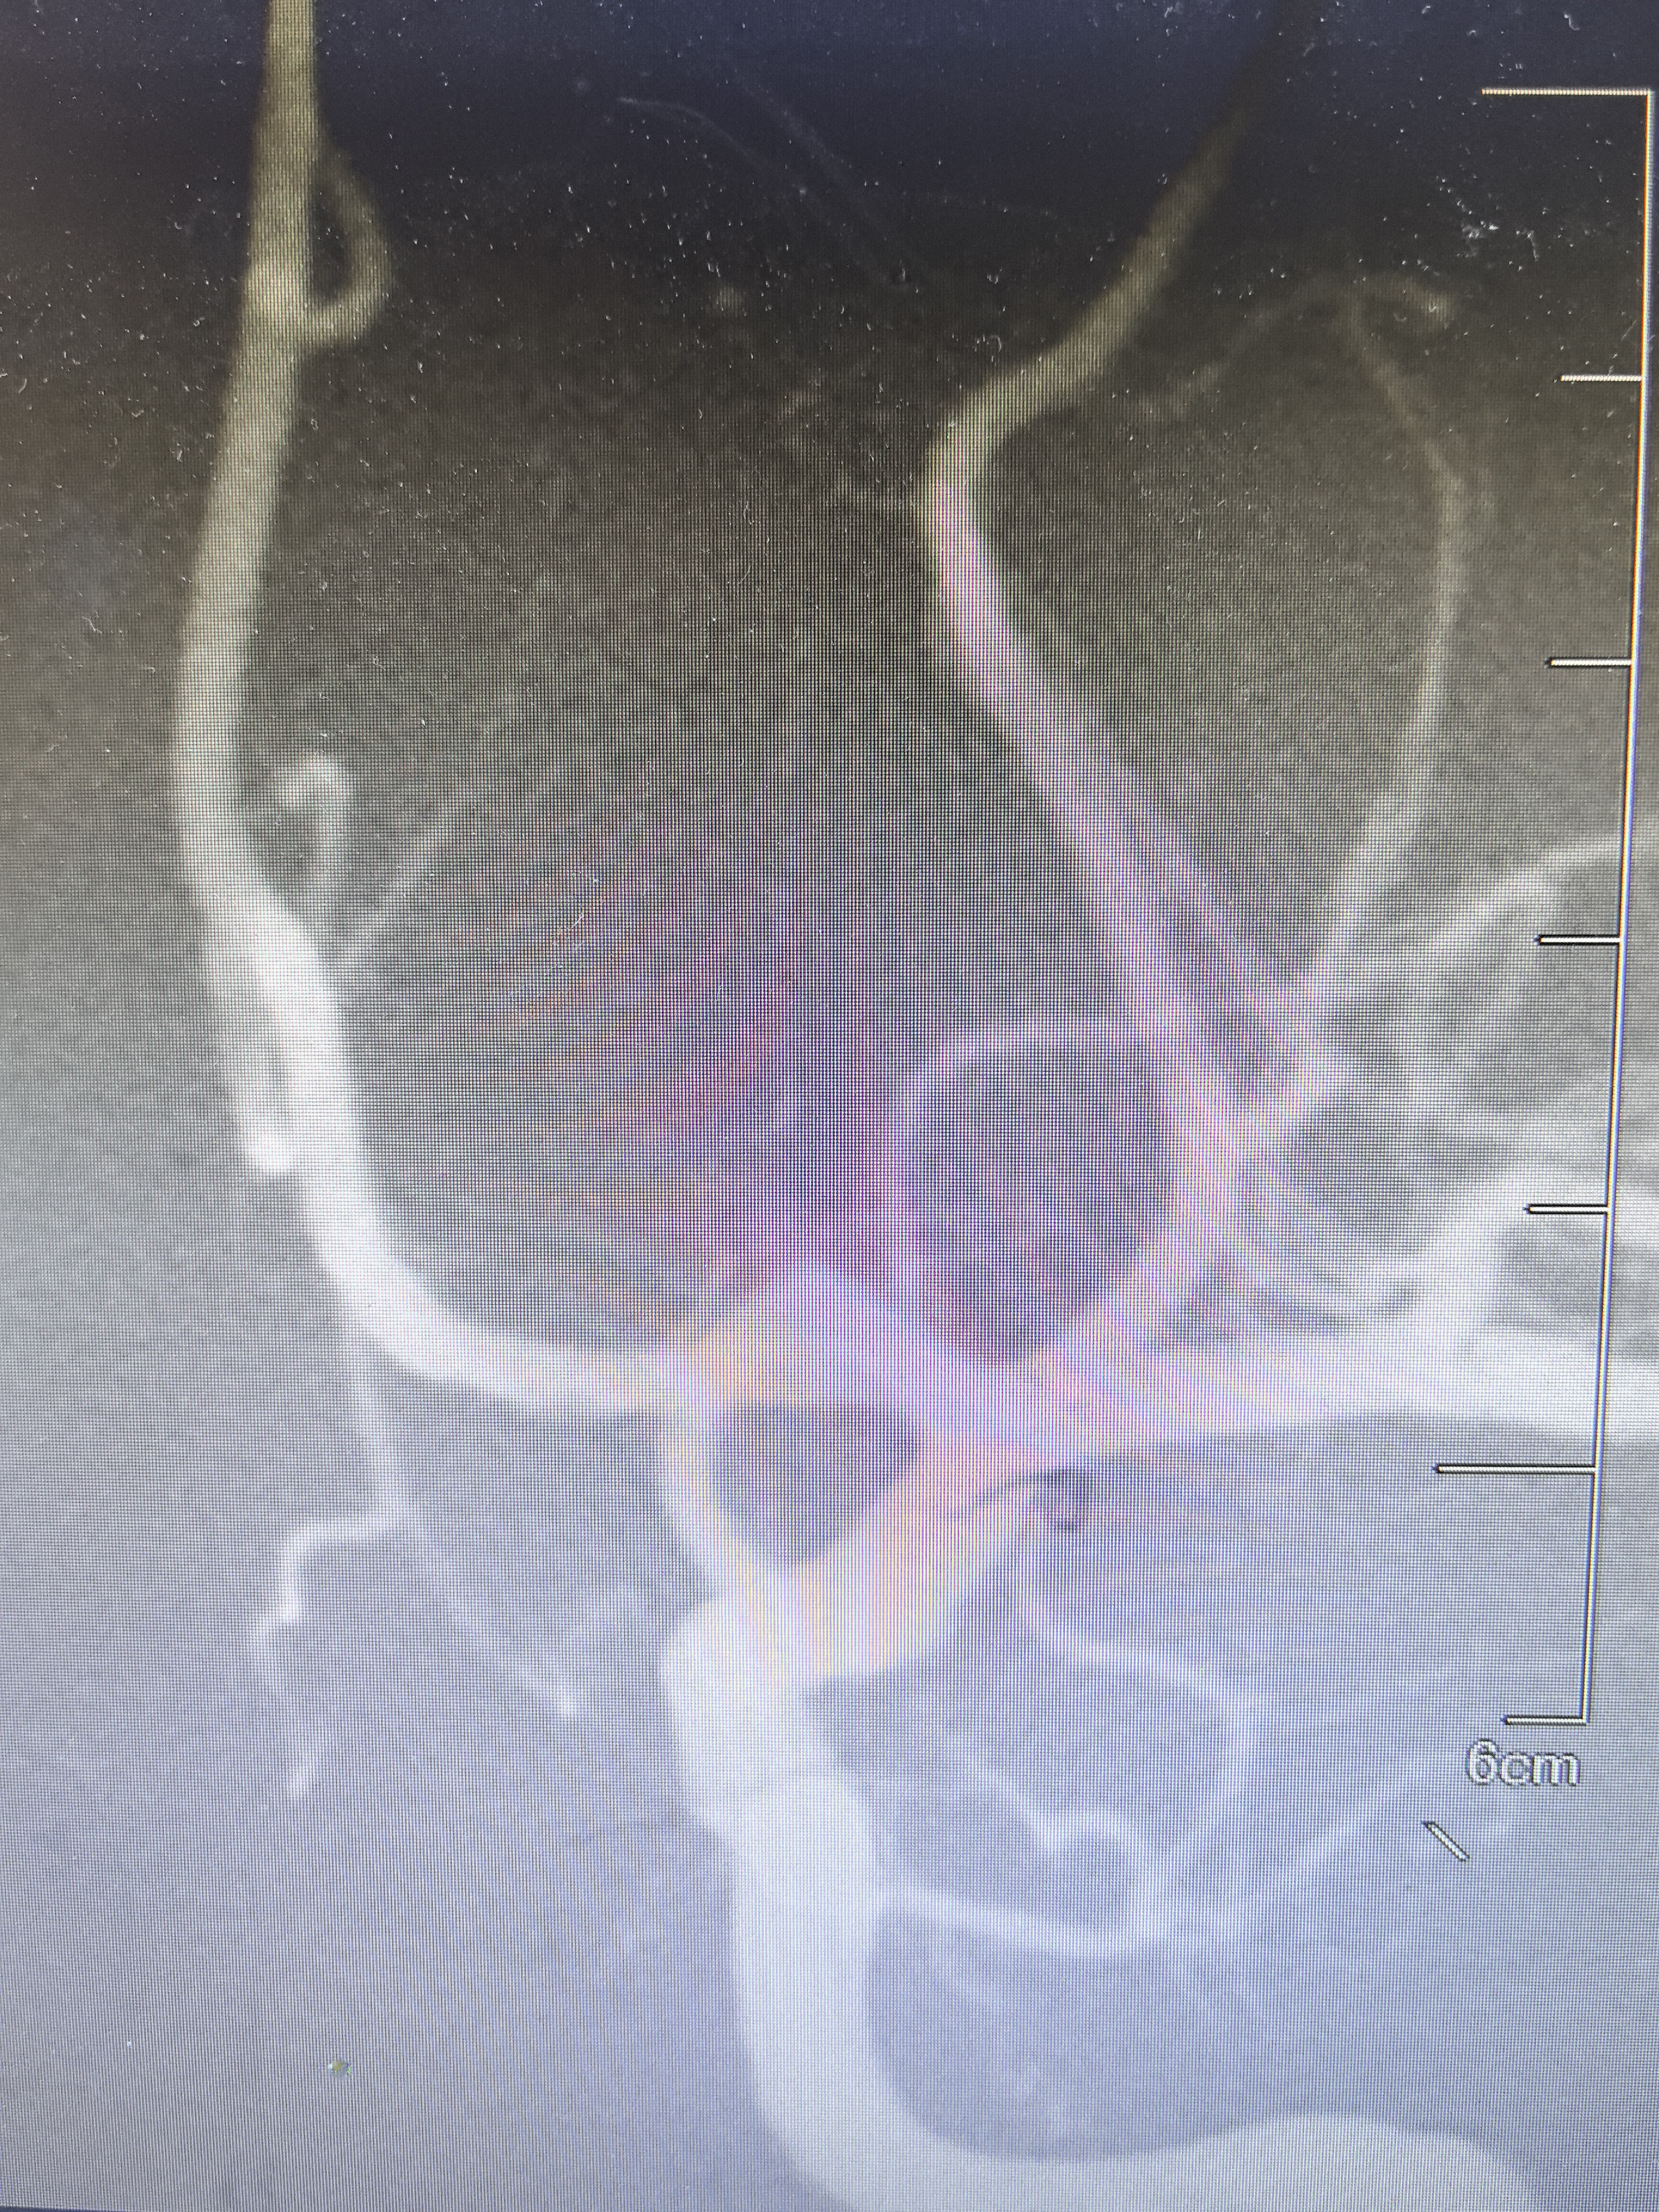

DSA显示左侧变异颞前早期分支起始部微小动脉瘤

路途下显示动脉瘤